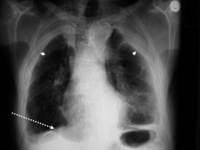

Asbestosis

Posterior-anterior view of the chest with 'en face' pleural changes in the mid zones on the right and left (arrows)

From the personal collection of Kenneth D. Rosenman MD